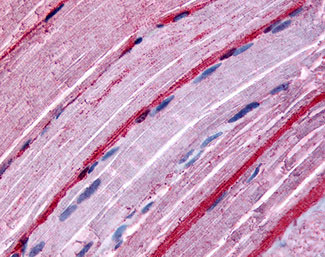

Anti-GRK5 antibody APR02011G IHC of human skeletal muscle. |